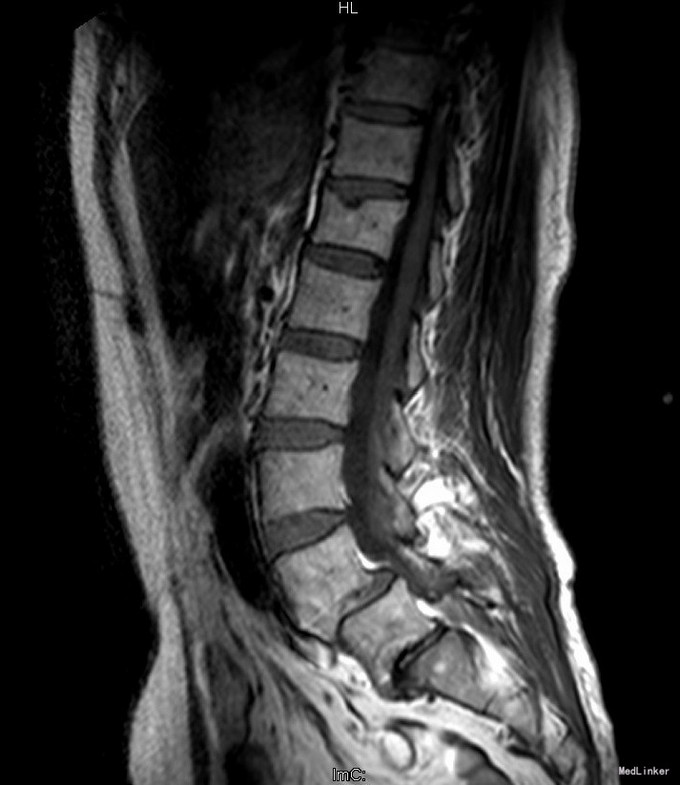

主诉:反复腰部疼痛20+年,加重伴双下肢胀痛麻木 现病史:患者于20+年前,因车祸行腰椎检查发现腰4椎体I°滑脱,并感腰部阵发性隐痛不适,一直未行特殊处理、4月前患者感腰部疼痛有所加重,并感双下肢阵发性胀痛麻木,久坐或弯腰后症状加重,以左下肢为甚,症状明显时难以直立行走,不伴畏寒发热、潮热盗汗等不适。10+天前患者在院外行理疗(具体不详),上述症状略有好转。在院外行腰椎x光摄片诊断为"腰4椎体II°滑脱,腰5椎体I°滑脱",故来我院就诊,门诊以"腰椎滑脱"收入住院

查体:脊柱外观无侧弯后突畸形,双下肢无肌肉萎缩。腰4-5、腰5骶1棘上棘旁轻压痛,伴左侧下肢放射;会阴部感觉未见异常,双侧小腿前外侧及足背足底感觉减退。腰椎前屈后伸及侧屈活动度正常;双下肢髂腰肌肌力4级,左侧直腿抬高试验阳性,加强试验阳性,左侧膝腱反射减弱,双侧病理征未引出。 辅助检查:院外腰椎正侧位片:腰4椎体II°滑脱,腰5椎体I°滑脱。

诊断:腰4椎II°滑脱症,腰5椎I°滑脱症 治疗:经后路腰4、5椎切开复位、椎管减压、Capstone椎间及后外侧人工骨+自体骨植骨融合、Legacy内固定术